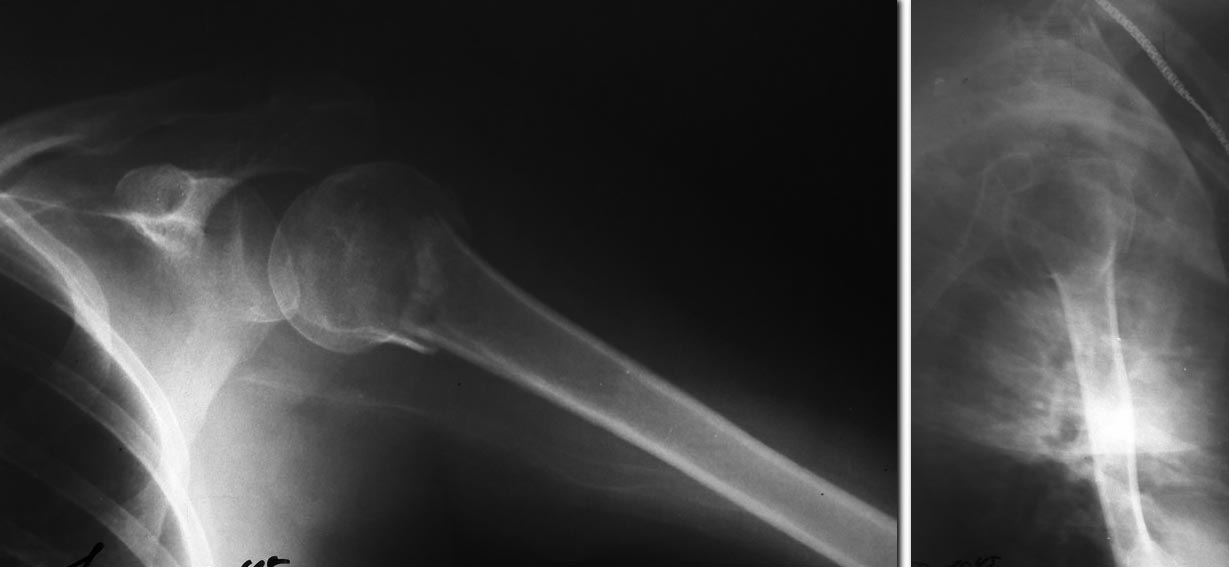

Контроль на отводящей подушке. Пока КТ не сделали.Завтра планируем. При

отсутствии повреждений вращательной манжеты по МРТ может и на

консервативном ведении остановимся.